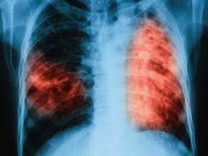

Los alumnos de 6to año, orientación Ciencias Naturales, abordaron el estudio de las enfermedades infectocontagiosas en el espacio de Salud, con la profesora Silvia Raffin. En las clases prestaron especial atención a la tuberculosis, endémica en nuestra región, y presentaron sus resultados en exposiciones orales.